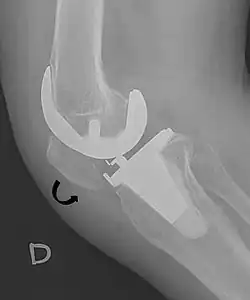

For recurrent patellar dislocations or cases with chronic instability, surgical intervention may be necessary. Patella stabilization surgery aims to restore proper kneecap tracking and reduce the risk of future dislocations.[4] Surgical options include reconstruction of the medial patellofemoral ligament (MPFL), realignment procedures such as osteotomy, and soft tissue adjustments around the patella.[4] MPFL reconstruction typically involves harvesting a hamstring tendon, commonly the gracilis, to create a new ligament that is positioned anatomically and secured with suture anchors.[4]

A patella alta is a high-riding (superiorly aligned) patella. An attenuated patella alta is an unusually small patella that develops out of and above the joint.

A patella baja is a low-riding patella. A long-standing patella baja may result in extensor dysfunction.[6]

The Insall-Salvati ratio helps to indicate patella baja on lateral X-rays, and is calculated as the patellar tendon length divided by the patellar bone length. An Insall-Salvati ratio of < 0.8 indicates patella baja.[7]